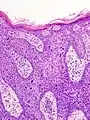

La maladie de Bowen est un carcinome épidermoïde (ou spinocellulaire) intra-épidermique (carcinome in situ), favorisé par le soleil et l'arsenic. Elle peut toucher la peau mais aussi les muqueuses[1]. Elle se présente sous la forme d'une lésion brun rougeâtre arrondie ou arciforme bien limitée dont la surface est un peu surélevée et squameuse[1]. Son diagnostic est histologique. Son évolution est très lente et la maladie présente un excellent pronostic de guérison. En revanche, en l'absence d'un diagnostic et d'un traitement approprié, elle évolue lentement mais sûrement vers un véritable carcinome épidermoïde invasif[1].